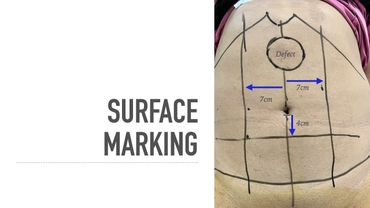

e-TEP RS with midline crossover at Hypogastrium

Similar videos: TEP RS with midline crossover at Hypogastrium

eTEP RS with midline crossover in hypogastrium for Primary Epigastric Hernia with divarication